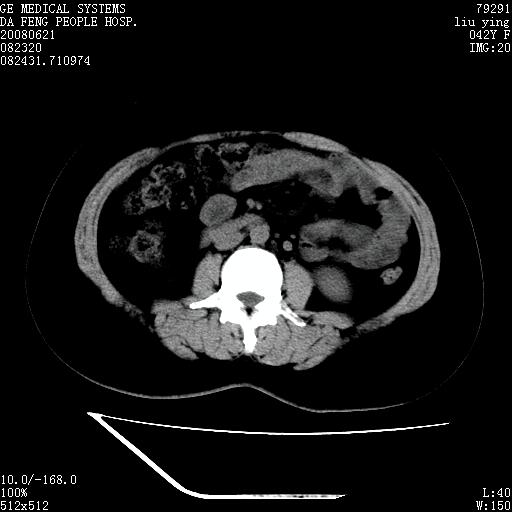

标题: CT14225:女性46岁。当地B超示肝内占位,来我院作CT检查。请 [打印本页]

标题: CT14225:女性46岁。当地B超示肝内占位,来我院作CT检查。请

速升速降,支持肝癌.脾体积增大,形态欠规整,请询问病史是否做过脾动脉栓塞.

速升速降,支持肝癌可能。

右叶肝癌灶;慢性胆囊炎,不除外占位;;副脾可能性

快进快出,符合肝癌表现-----------

肝内结节强化特点符合原发性肝癌表现,脾脏改变考虑为增大及先天发育所致。

动脉期病原灶明显强化高于肝密度且中央有无强化区,静脉期强化程度下降明显,延迟低于肝密度,考虑肝腺瘤可能性大,

肝内结节强化特点:快进快出符合原发性肝癌表现

此患者虽然符合快进的特点,却不符合快出的特点,因为门脉期几乎是等密度,不符合肝癌的增强表现,所以我考虑肝局灶性结节增生可能性大